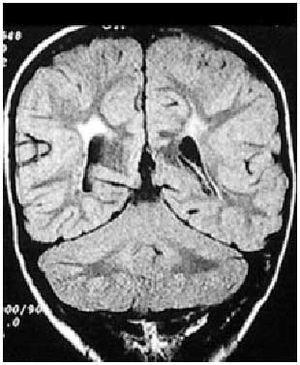

Aunque se han descrito diferentes hallazgos neurorradiológicos en casos aislados, la leucomalacia periventricular (fig. 4) es el patrón anatomopatológico y radiológico más común.

Fig. 4. RNM cerebral potenciada en T1, corte coronal. Leucomalacia periventricular en RNPT con diparesia espástica.